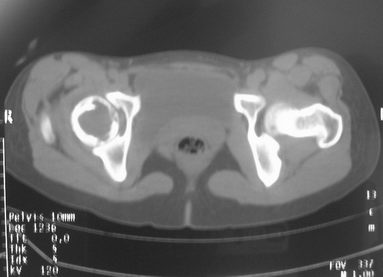

女,31岁,右髋部疼痛半年,加剧两天不能行走

hhcckk发言:右股骨颈囊状骨质破坏,骨皮质变薄,周围硬化边不明显

我与楼主考虑的不太一样,我考虑骨巨的可能性更大

dyqct发言:支持右股骨头、颈骨巨细胞瘤可能性大(跨越骺线).

拾荒者分析:该病例囊肿透亮度较高,骨膨胀轻微,还是要首先考虑骨囊肿。至于与骨细胞瘤的鉴别,影像鉴别困难。我想,发病年龄及临床症状可能是主要参考点。